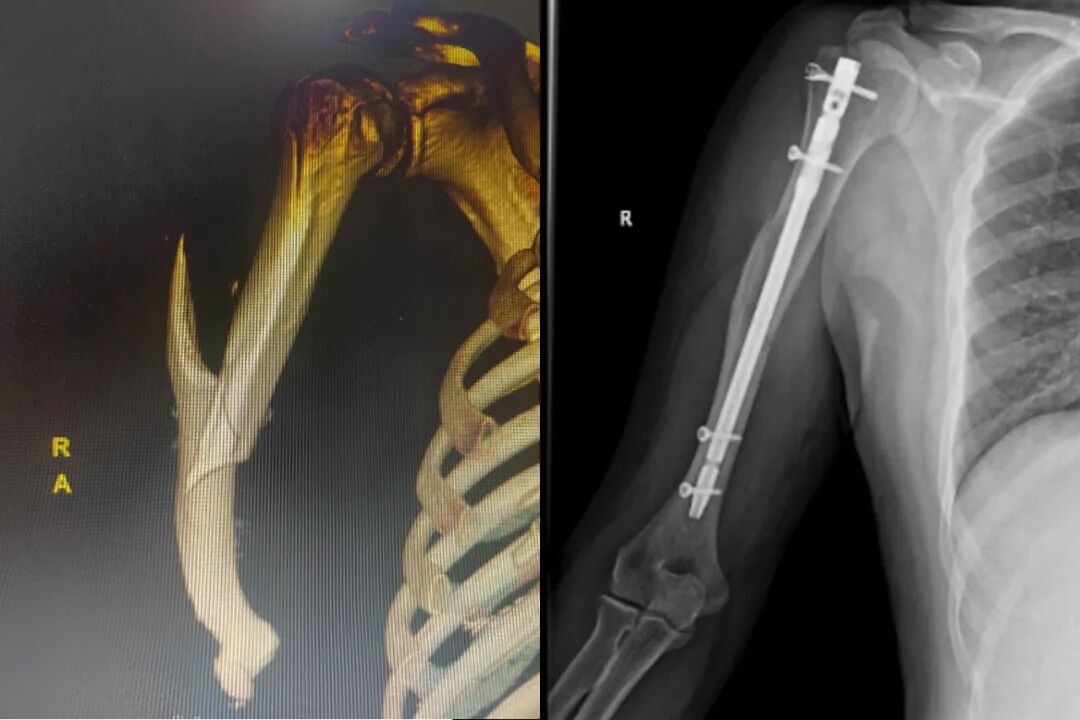

开展的特色技术项目有:1.断肢、断指再植及四肢急慢性创面修复治疗;2.肩关节周围、锁骨骨折治疗及周围韧带重建;3.肱骨骨折、肘关节骨折内固定治疗及功能重建;4.尺桡骨骨折、腕关节骨折、指掌骨骨折内固定治疗及韧带断裂修复重建;5.胫骨骨折、踝关节骨折、足骨及跗骨骨折内固定治疗;6.四肢腱鞘囊肿手术治疗及微创治疗、四肢腱鞘炎手术治疗及微创治疗;7.踝关节周围韧带修复重建;8.踝关节骨性关节炎关节融合及关节镜治疗;9.四肢慢性骨髓炎手术治疗;10.糖尿病足及急慢性溃疡规范化治疗;11.电、化学烧伤及一般烧烫伤修复重建及规范化治疗;12.周围神经松解及规范化治疗;13.四肢疤痕松解及功能重建规范化治疗;14.踇外翻及足病矫形功能重建及规范化治疗;15.四肢骨缺损骨及修复重建规范化治疗;16.体表肿瘤切除术后创面修复重建;17.四肢疼痛范化治疗及创伤骨科、手外科、足踝外科、烧伤外科及整形外科、修复重建外科;18.小儿骨科等疾病诊治有较丰富临床经验。